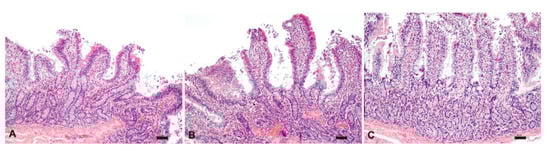

Based on the histological evaluation, the tissue and cell morphology of intestinal mucosa retain similar features as those described at time zero for about 3 h by being kept at 25 °C in PBS. In general, when performing ex vivo tests, the aspect related to the conservation and degenerative processes is considered marginal. However, alterations of the intestinal mucosa that occur over time, as well as the presence of inflammation as a “background lesion”, could invalidate the success of these tests; therefore, it would be prudent to carry out a preliminary histological evaluation in order to consider any intrinsic “bias”.

For the ex vivo permeation test, the intestine was treated with fluorescein-labeled SLN (F-SLN) and the fluorescein solution; an untreated intestinal mucosa was also used as a control. In this case, histological analysis of the untreated intestinal mucosa at time zero also revealed the presence of a moderate inflammatory infiltrate.

Diffuse signals were observed in the samples analyzed at 1 h both in the mucosa treated with the fluorescein solution and in that treated with F-SLN, probably related to the uptake of enterocytes and/or inflammatory cells present in the lamina propria of both free fluorescein and labeled SLN (Figure 9).

Figure 9.

Ex vivo permeation test on intestinal tissue after 1 h: untreated intestinal mucosa, intestinal mucosa treated with free fluorescein solution, and intestinal mucosa treated with F-SLN. Signal (green) / Hoechst 33342 nuclei (blue). Bar: 50 µm.

Fluorescence signals were observed in the samples analyzed after 2 h both in the untreated control mucosa and in the free fluorescein and SLN treated tissues (Figure 10). Similar results were also observed at 3 h. Therefore, the detection of fluorescence signals in the untreated mucosa could be related to the high inflammatory infiltrate consisting, in addition to lymphocytes and plasmacells, of macrophage cells capable of engulfing cellular debris or degradation products such as lipofuscins, which by their intrinsic nature could emit fluorescence [46].

Figure 10.

Ex vivo permeation test on intestinal tissue after 2 h: untreated intestinal mucosa, intestinal mucosa treated with free fluorescein solution, intestinal mucosa treated with F-SLN. Signals (green) / Hoechst 33342 nuclei (blue). Bar: 50 µm.